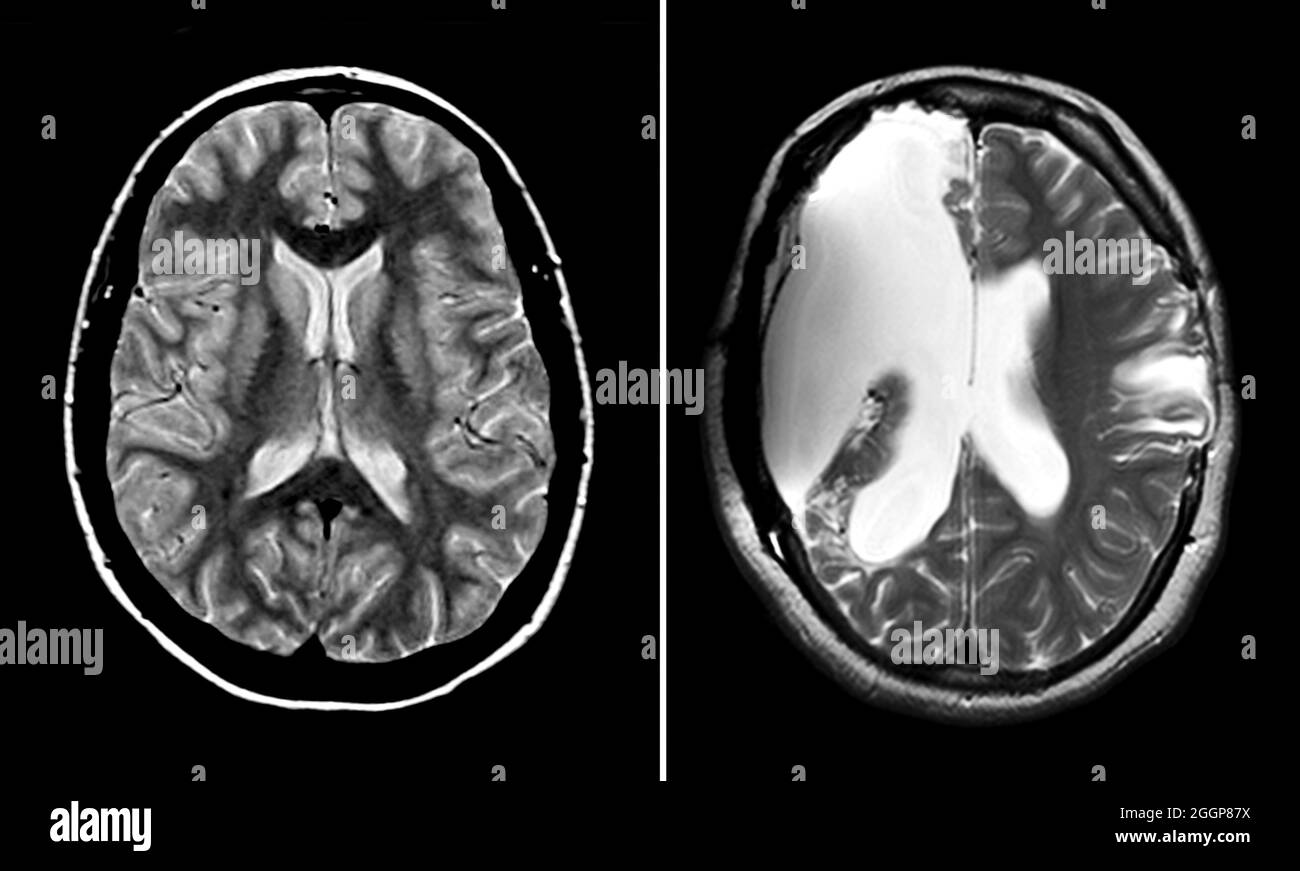

Source: gsmdccryf.pages.dev IRM du cerveau normal (à gauche) et d'un cerveau avec sclérose en plaques aiguë (à droite).Sur , @Claudia.L J'ai fait ma dernière IRM le mois dernier, j'en fais tous les ans Dans ces conditions, il est le plus souvent proposé.

Source: komedookr.pages.dev Axial T1 MRI images showing periventricular lesions of various... Download Scientific Diagram , Vivre avec la sclérose en plaques - sep et irm normal??? Des milliers de discussions. L'examen IRM est essentiel au diagnostic de sclérose en plaques